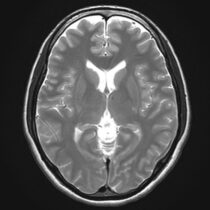

VSRAD

最近、物忘れや記憶力の低下はありませんか?

当院ではVSRAD(ブイエスラド)というアプリケーションを用いて、同年代の正常脳と比較して、海馬(かいば)がどの程度委縮しているかを統計的に解析し評価することができます。

アルツハイマー型認知症では、この海馬の萎縮が関係しており、早期のアルツハイマー型認知症の診断に役立てています。